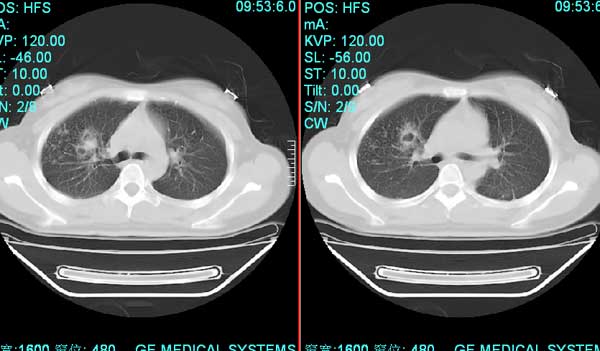

以下是引用pujunzhi在2008-7-1 20:03:00的发言:[br]支持楼主意见!两肺继发性肺结核伴多发空洞形成。